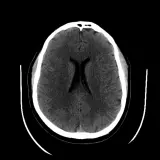

Over 2,100 interactive radiology cases, curated by radiologists for your level of training. Scroll, window, and view cases full screen — just like on PACS. Click linked findings in each writeup to jump straight to them on the image. Cases include sample reports, a focused discussion section, original illustrations, and videos.

Des cas entièrement interactifs avec les outils attendus d'un PACS — défilement, fenêtrage, zoom, déplacement, mesures, ROI et mode plein écran.

Des annotations détaillées mettent en évidence les résultats clés directement sur les cas. Cliquez sur les résultats liés dans les descriptions de cas pour accéder à leur emplacement exact sur l'examen.